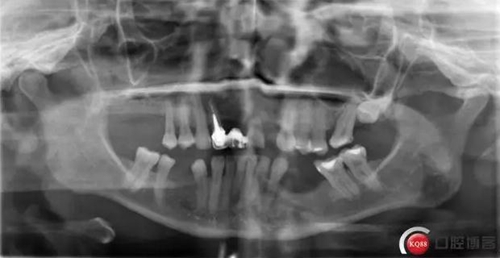

種植體和下頜頦神經(jīng)“近距離接觸”一例 科貿(mào)嘉友收錄

看了黃生醫(yī)生的 “一例避開下齒槽神經(jīng)管種植病例 “ 一文, 想起自己有一例植體靠近下頜頦孔的病例。找出來(lái)和大家分享一下。

術(shù)前